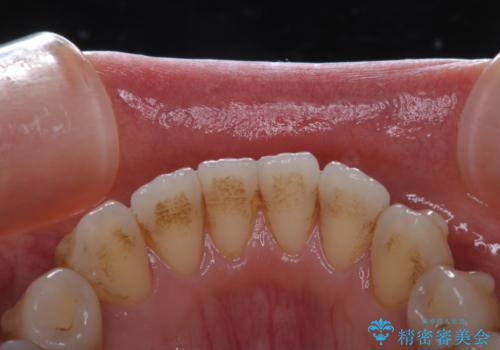

- インビザライン矯正治療中に頑固に付着した着色を取りたいとのことでした。PMTC60分コースを行いました。

アタッチメントが歯に付くと、表面が凸凹し磨き残しが多くなったりと、プラークや歯石・着色がつきやすくなることがあります。

矯正治療中もPMTCを定期的に行い、専門的な機械でしっかりと汚れを除去することがおススメです。